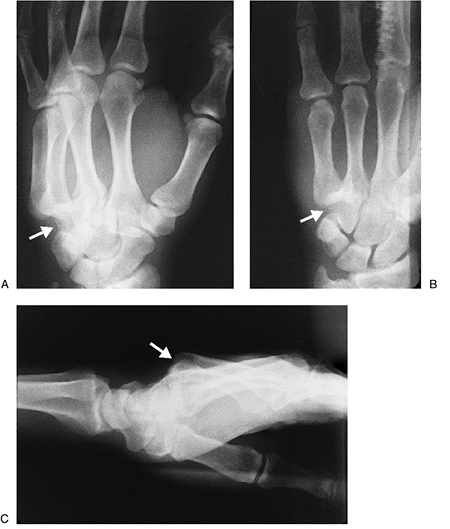

In complete dislocations, the radiographic findings may be minimal in the anteroposterior view.

The oblique view usually demonstrates widening of the joint space, and the lateral view may show the complete dislocation.

Lateral or dorsal displacement of the sesamoid in the oblique and lateral views also is an important finding.

A tangential or Brewerton view of the

fractures in the region of the metacarpal head (Figure 10-14).

Figure 10-12 Complete dorsal dislocation of the index finger joint. (A–B) Extended and ulnar-deviated index finger. (C)

The head and neck of the dislocated metacarpal is trapped by the

ligaments, and the palmar plate, and the lumbrical. -

Figure 10-13 (A) Clinical appearance of a complete and locked dorsal dislocation of the MCP joint of the index finger. (B) Hyperextension at the MCP joint, and ulnar deviation of the index finger.

Figure 10-14 X-ray appearance of a dorsal dislocation of the index finger MCP joint. (A) The AP view shows only minimal changes at the MCP joint (arrow). (B) The oblique view shows a widened MCP joint space and some dorsal displacement of the proximal phalanx (arrow). (C) The lateral view shows a complete dislocation (arrow).